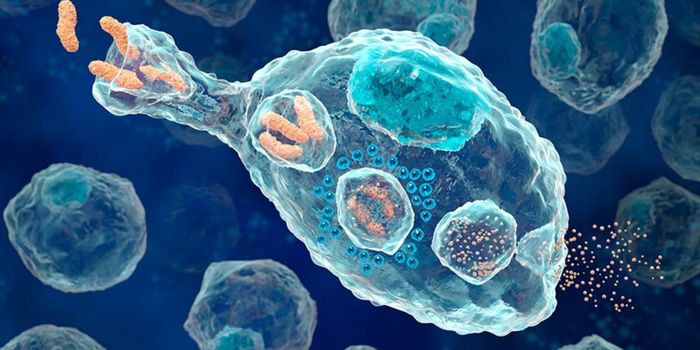

DEC 19, 2015ImmunologyDendritic cells use phagocytosis to break up molecules from pathogens to present on their cell surface to warn other lym ...